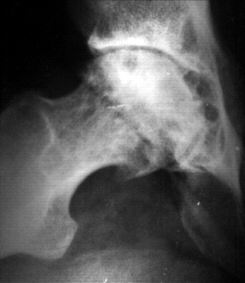

Остеонекроз головки бедренной кости

Разрушение головки бедренной кости на фоне ишемии. Причины: травма, тромбофилия, длительный приём глюкокортикоидов, серповидноклеточная анемия, системная красная волчанка, гиперлипидемия, хроническая почечная недостаточность, сахарный диабет, алкоголизм, аутоиммунные заболевания и др. На долю остеонекроза приходится 1,5—4,7 % случаев всей ортопедической патологии, 5—18 % тотальных эндопротезирований тазобедренного сустава. Чаще развивается у мужчин в возрасте 30—50 лет. У 75—80 % пациентов в течение 3—4 лет развивается коллапс головки бедренной кости, требующий тотального эндопротезирования. Пациенты жалуются на боли в паху, ягодицах или коленных суставах. При осмотре выявляется болезненность и ограничение движения при повороте бедра внутрь[2][3].